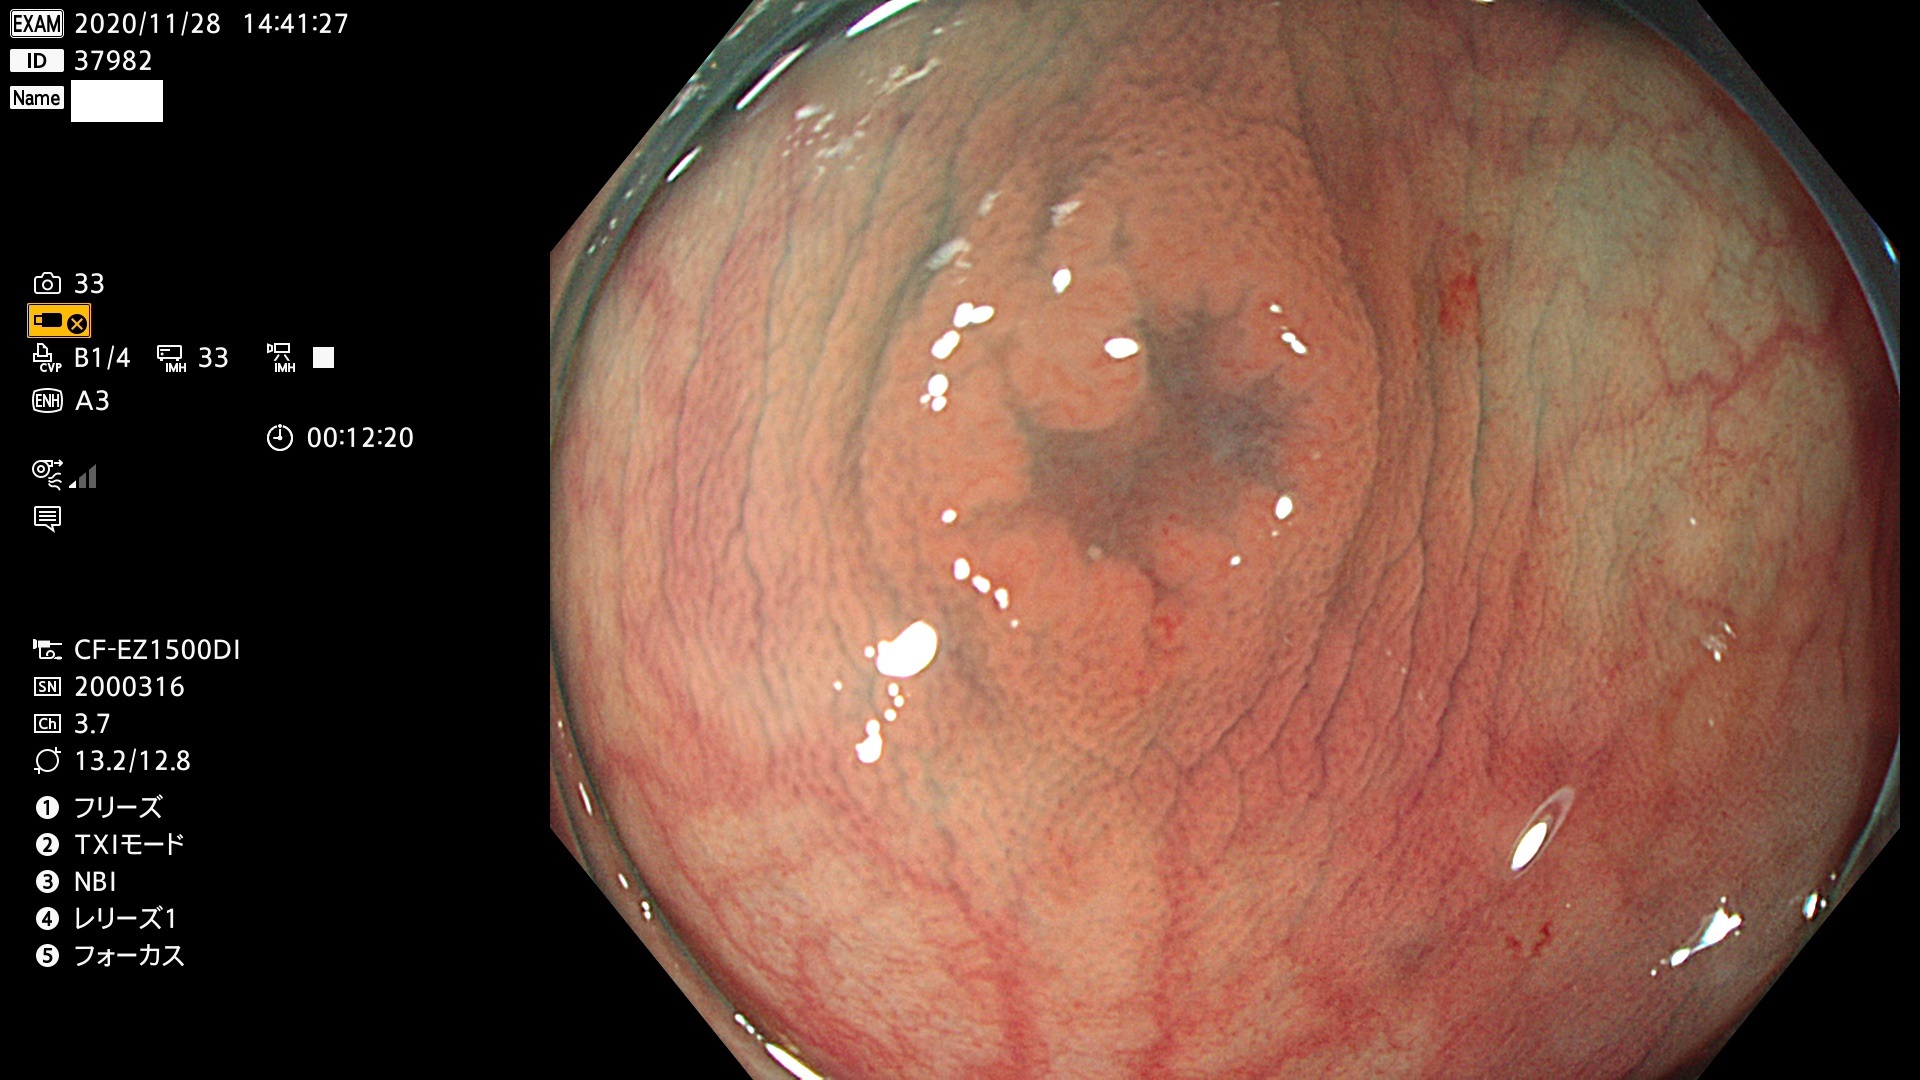

発見困難で危険性の高い平坦型病変(上記100名より抽出)

37900 37902 37903 37904 37905 37906 37907 37909 37910 37911 37912 37913 37914 37915 37916 37917 37919 37921 37922 37923 37926 37928 37929 37930 37931 37933 37934 37935 37936 37937 37938(SSAPのみ) 37939 37940 37941 37942 37943 37946 37947 37948 37949 37951 37952 37953(SSAPのみ) 37955 37956 37957(SSAPのみ) 37958(SSAPのみ) 37960 37962 37963 37964 37966 37967 37968 37971 37972 37973 37975 37976 37977 37979 37982 37983 37984 37985 37986 37987 37988 37989 37990 37991 37992 37993 37994 37995 37996 37998 37999